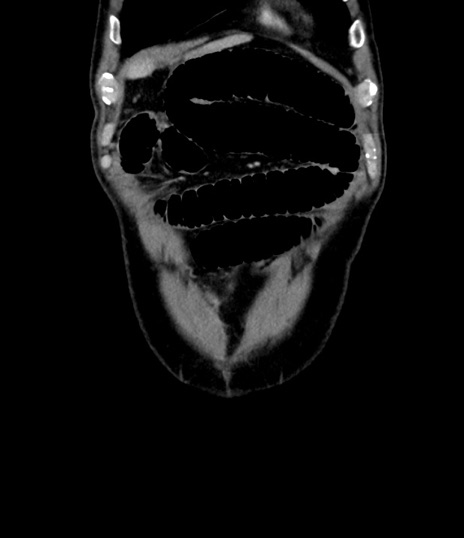

症例8(冠状断像)

【症例】 60歳代男性

【主訴】 黒色吐物

【現病歴】 4日前から嘔気自覚、2日前の朝食後にも嘔気あり、自分で手で嘔吐反射起こし嘔吐したところ血が混ざっていたため受診。

【既往歴】 5年前汎発性腹膜炎を伴う急性虫垂炎で手術、高血圧、前立腺肥大症、高脂血症

【身体所見】 腹部正中に手術癩痕あり 腹部平坦・軟圧痛なし膨満感あり

【データ】WBC 8400、CRP 4.54